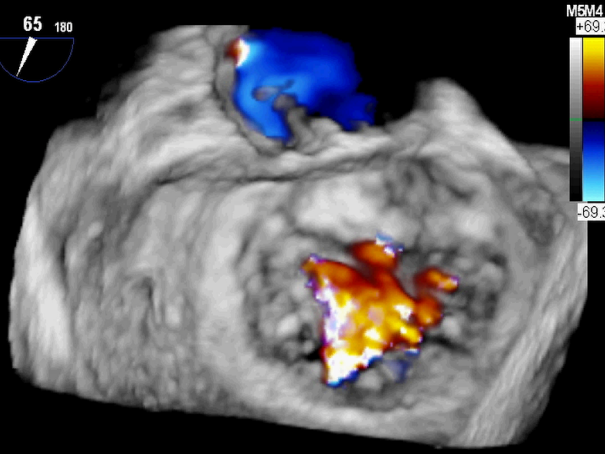

患者术前TEE提示重度功能性二尖瓣反流,反流位于A2/P2,瓣膜活动度可,后瓣较短,手术难度较高(图1)。手术采用经典股静脉房间隔途径,房间隔穿刺后植入24F导引导管及二尖瓣夹输送系统,在TEE引导下准确植入一枚二尖瓣夹,瓣膜夹位置稳定。瓣膜夹植入后反流明显减轻至轻度(图2),二尖瓣跨瓣平均压力阶差2mmHg,双孔化形成,遂移除输送系统。

图2:植入一枚瓣膜夹之后二尖瓣反流明显减轻